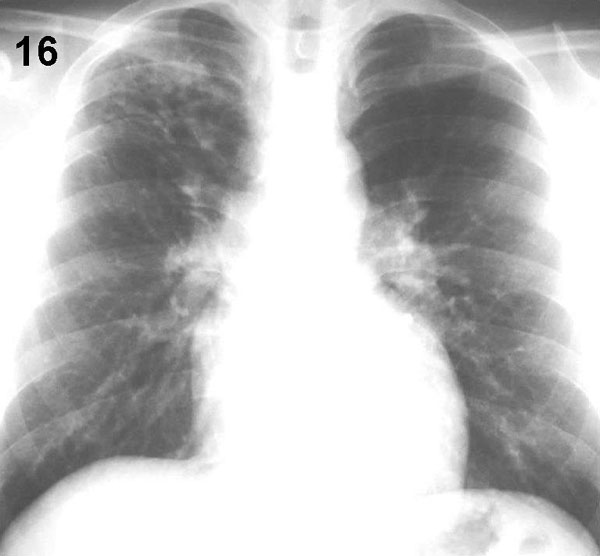

ESQUEMA 16 Comentario placa 16 En la región subclavia derecha hay numerosa sombras acinares que, a diferencia de las anteriores, sólo confluyen parcialmente. Son frecuentemente de naturaleza inflamatoria y una causa frecuente, que debe siempre investigarse con otros exámenes, es la tuberculosis. |